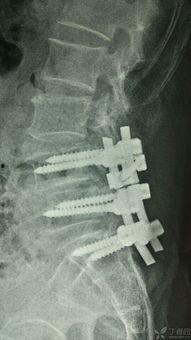

5. 固定:为了防止滑脱再次发生,医生会在椎体上安装金属钉、棒或钢板等固定装置。